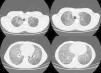

En el momento del ingreso en la unidad de neumología el paciente presentaba disnea basal gradoi-ii. A la exploración se apreciaba buena coloración de la piel y de las mucosas y acropaquías. La saturación basal de O2 era del 93% y la auscultación mostraba buen murmullo vesicular, sin ruidos sobreañadidos. La espirometría mostró FEV1: 44%, FVC: 47%, FEV1/FVC:79, MMEF:29%, si bien la colaboración del paciente fue incompleta. La radiografía de tórax mostraba extenso patrón alveolointersticial bilateral con afectación multilobar. Durante la hospitalización se completó con tomografía computarizada de alta resolución (TACAR), en la que se observó marcada alteración del parénquima pulmonar, con extensas áreas en vidrio deslustrado distribuidas por todos los lóbulos aunque con predomino basal, sobre el que se superponía engrosamiento septal, conformando un patrón en empedrado o crazy-paving (fig. 1). Además se apreciaban áreas de panalización en el parénquima pulmonar subpleural a nivel de ambos lóbulos superiores, aunque de predominio derecho.

Los hallazgos radiológicos en TACAR más frecuentes en la NL son4,5: presencia de condensación de bajo coeficiente de atenuación (entre –75 y –35UH), muy específica y frecuente en la NL endógena1, opacidades en vidrio deslustrado, patrón en empedrado (crazy-paving) y presencia de opacidades centrolobulillares. Además, en ella la afectación pulmonar tiene un predominio basal4.

El patrón en empedrado se describió inicialmente en la proteinosis alveolar4, si bien posteriormente se ha comprobado que puede aparecer en multitud de procesos, como en la sarcoidosis, la neumonía intersticial no específica, la neumonía organizada (tanto en la neumonía organizada criptogenética como en la bronquiolitis obliterante con neumonía organizada), infecciones pulmonares (principalmente víricas y por micoplasma), neoplasias como el carcinoma bronquioalveolar, la hemorragia, el edema pulmonar y la NL.